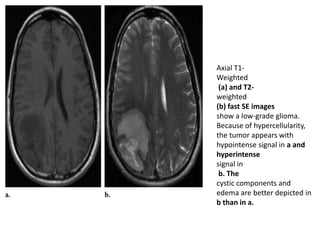

Axial T1-

Weighted

(a) and T2-

(b) fast SE images

show a low-grade glioma.

Because of hypercellularity,

the tumor appears with

hypointense signal in a and

hyperintense

signal in

b. The

cystic components and

edema are better depicted in

b than in a.